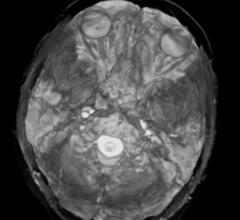

Magnetic Resonance Imaging (MRI)

The U.S. magnetic resonance imaging (MRI) market has been stable for the last few years. With an estimated value of $1.25 billion, the market has been flat with very low, if any, growth. It is predominantly a replacement market, with the majority of hospitals and imaging facilities upgrading older systems to newer ones. From a field strength standpoint, 1.5T and 3.0T systems dominate the market — approximately 65 and 35 percent, respectively.

The four MRI vendors fully ranked by KLAS are all within five points of each other as the MRI market becomes increasingly competitive. The newly released KLAS report MRI 2013: Sorting through the Noise examines what differentiates these vendors from one another, including their strengths and weaknesses.

The average age of installed MRI scanners in the United States has increased from 8.7 years in 2010 to 11.4 years in 2013, according to a new market research report by IMV Medical Information Division.